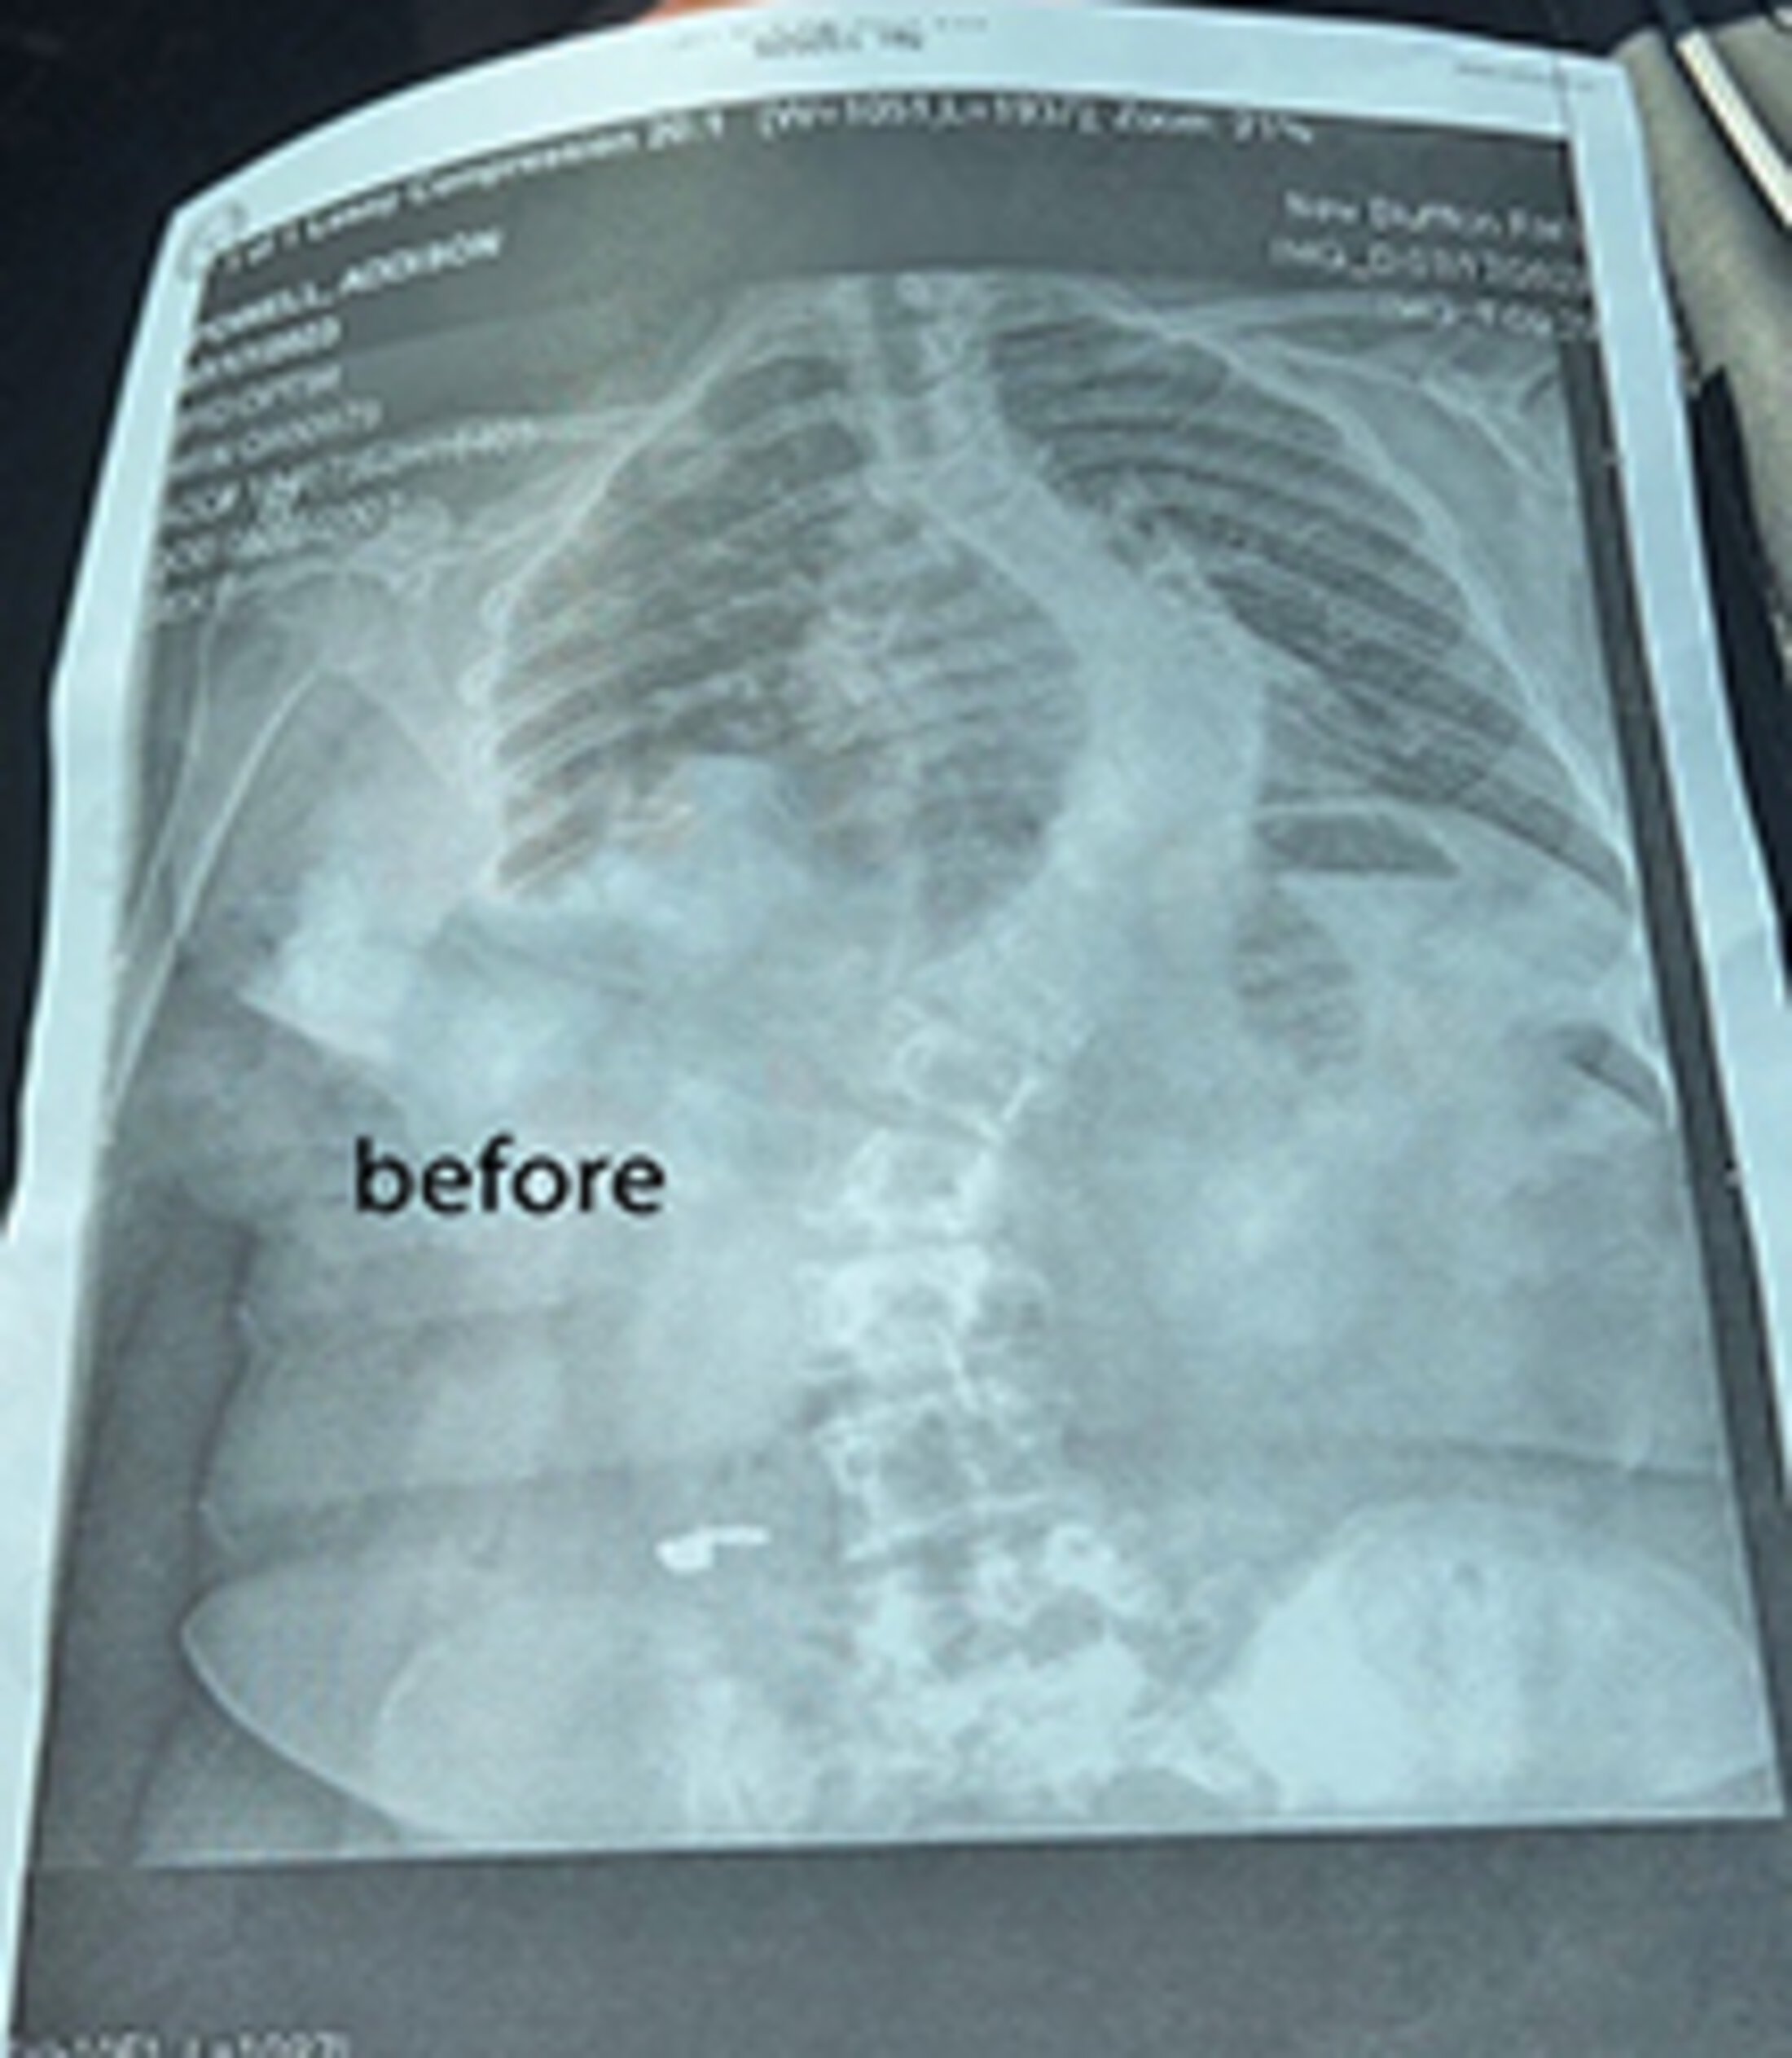

Before X-rays show the severity of Addy Powell’s scoliosis. Her condition was helped with surgery by Dr. Robert Ravinsky and his ortho team. Photos Provided

In January, Addy underwent a complex all-day surgery that straightened her spine and corrected her severe scoliosis. Performed by MUSC spinal surgeon Robert Ravinsky, M.D., the procedure saved her from possible paralysis by the age of 25. "My scoliosis was so bad that it was considered a spinal deformity," Addy said.

Scoliosis is characterized by an "S" or "C" curve in the spine and can range from mild to severe. At age 13, Addy was diagnosed with a mild form, but because she was still growing, she couldn't wear a back brace. Her parents were nervous. "We knew it was not good," said mom, Janet Powell. "Doctors made multiple attempts to perform an MRI, but Addy's anxiety and claustrophobia prevented them from succeeding."

Addy also continued to play soccer for her middle- and high school teams, but by her freshman year, her condition had worsened, and she was having muscle spasms in her left shoulder blade. Her spine was “super-twisted” and curved, so much so that she was unable to wear clothing with a zipper.